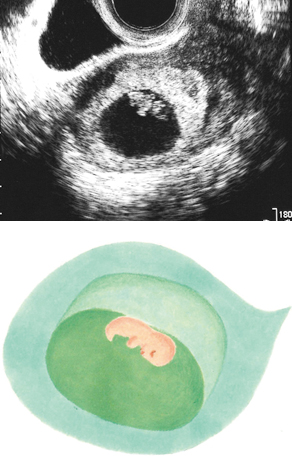

妊娠7週ころのエコー写真を見てみよう

頭部と胴の区別がついてきます

頭部と胴の区別がついてきて、2頭身くらいになります。将来の手や足の部分がわかってくるでしょう。のちに胎盤となる絨毛(じゅうもう)組織も少しずつ厚みを増して、白く見えることがあります。